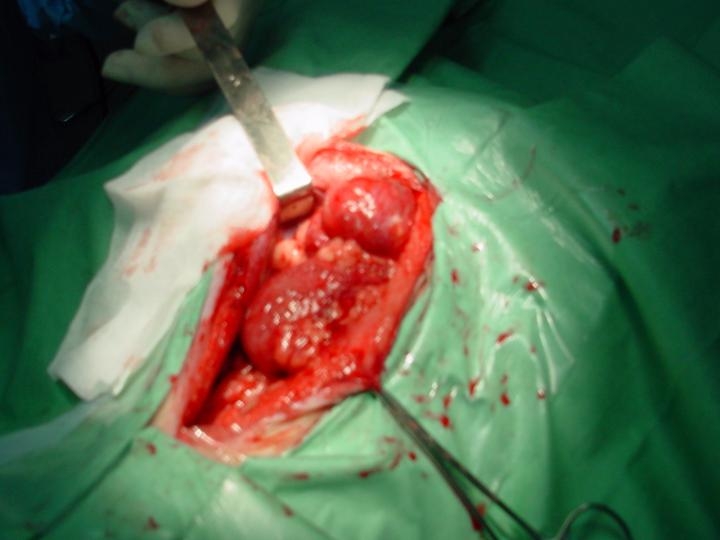

Laparotomia Mediana. Quisto Praprostático: Fez-se drenagem colocando uma sonda de Foley no parênquima prostático realizando assim a drenagem do abdomen posterior.

Laparotomia Mediana. Omentalização do quisto paraprostático. Para exteriorizar o quisto paraprostático fizemos extracção da bexiga. Fizemos punção com agulha e seringa e retiramos o lÃquido do quisto. Fizemos duas incisões e com aspirador fez-se a aspiração da totalidade dos lÃquidos. Fizemos dois túneis; um dorsal e outro ventral à uretra. Pelos túneis fez-se a passagem de um cordão epiplon à volta da uretra que foi suturado sobre si mesmo aplicando assim a técnica de White.